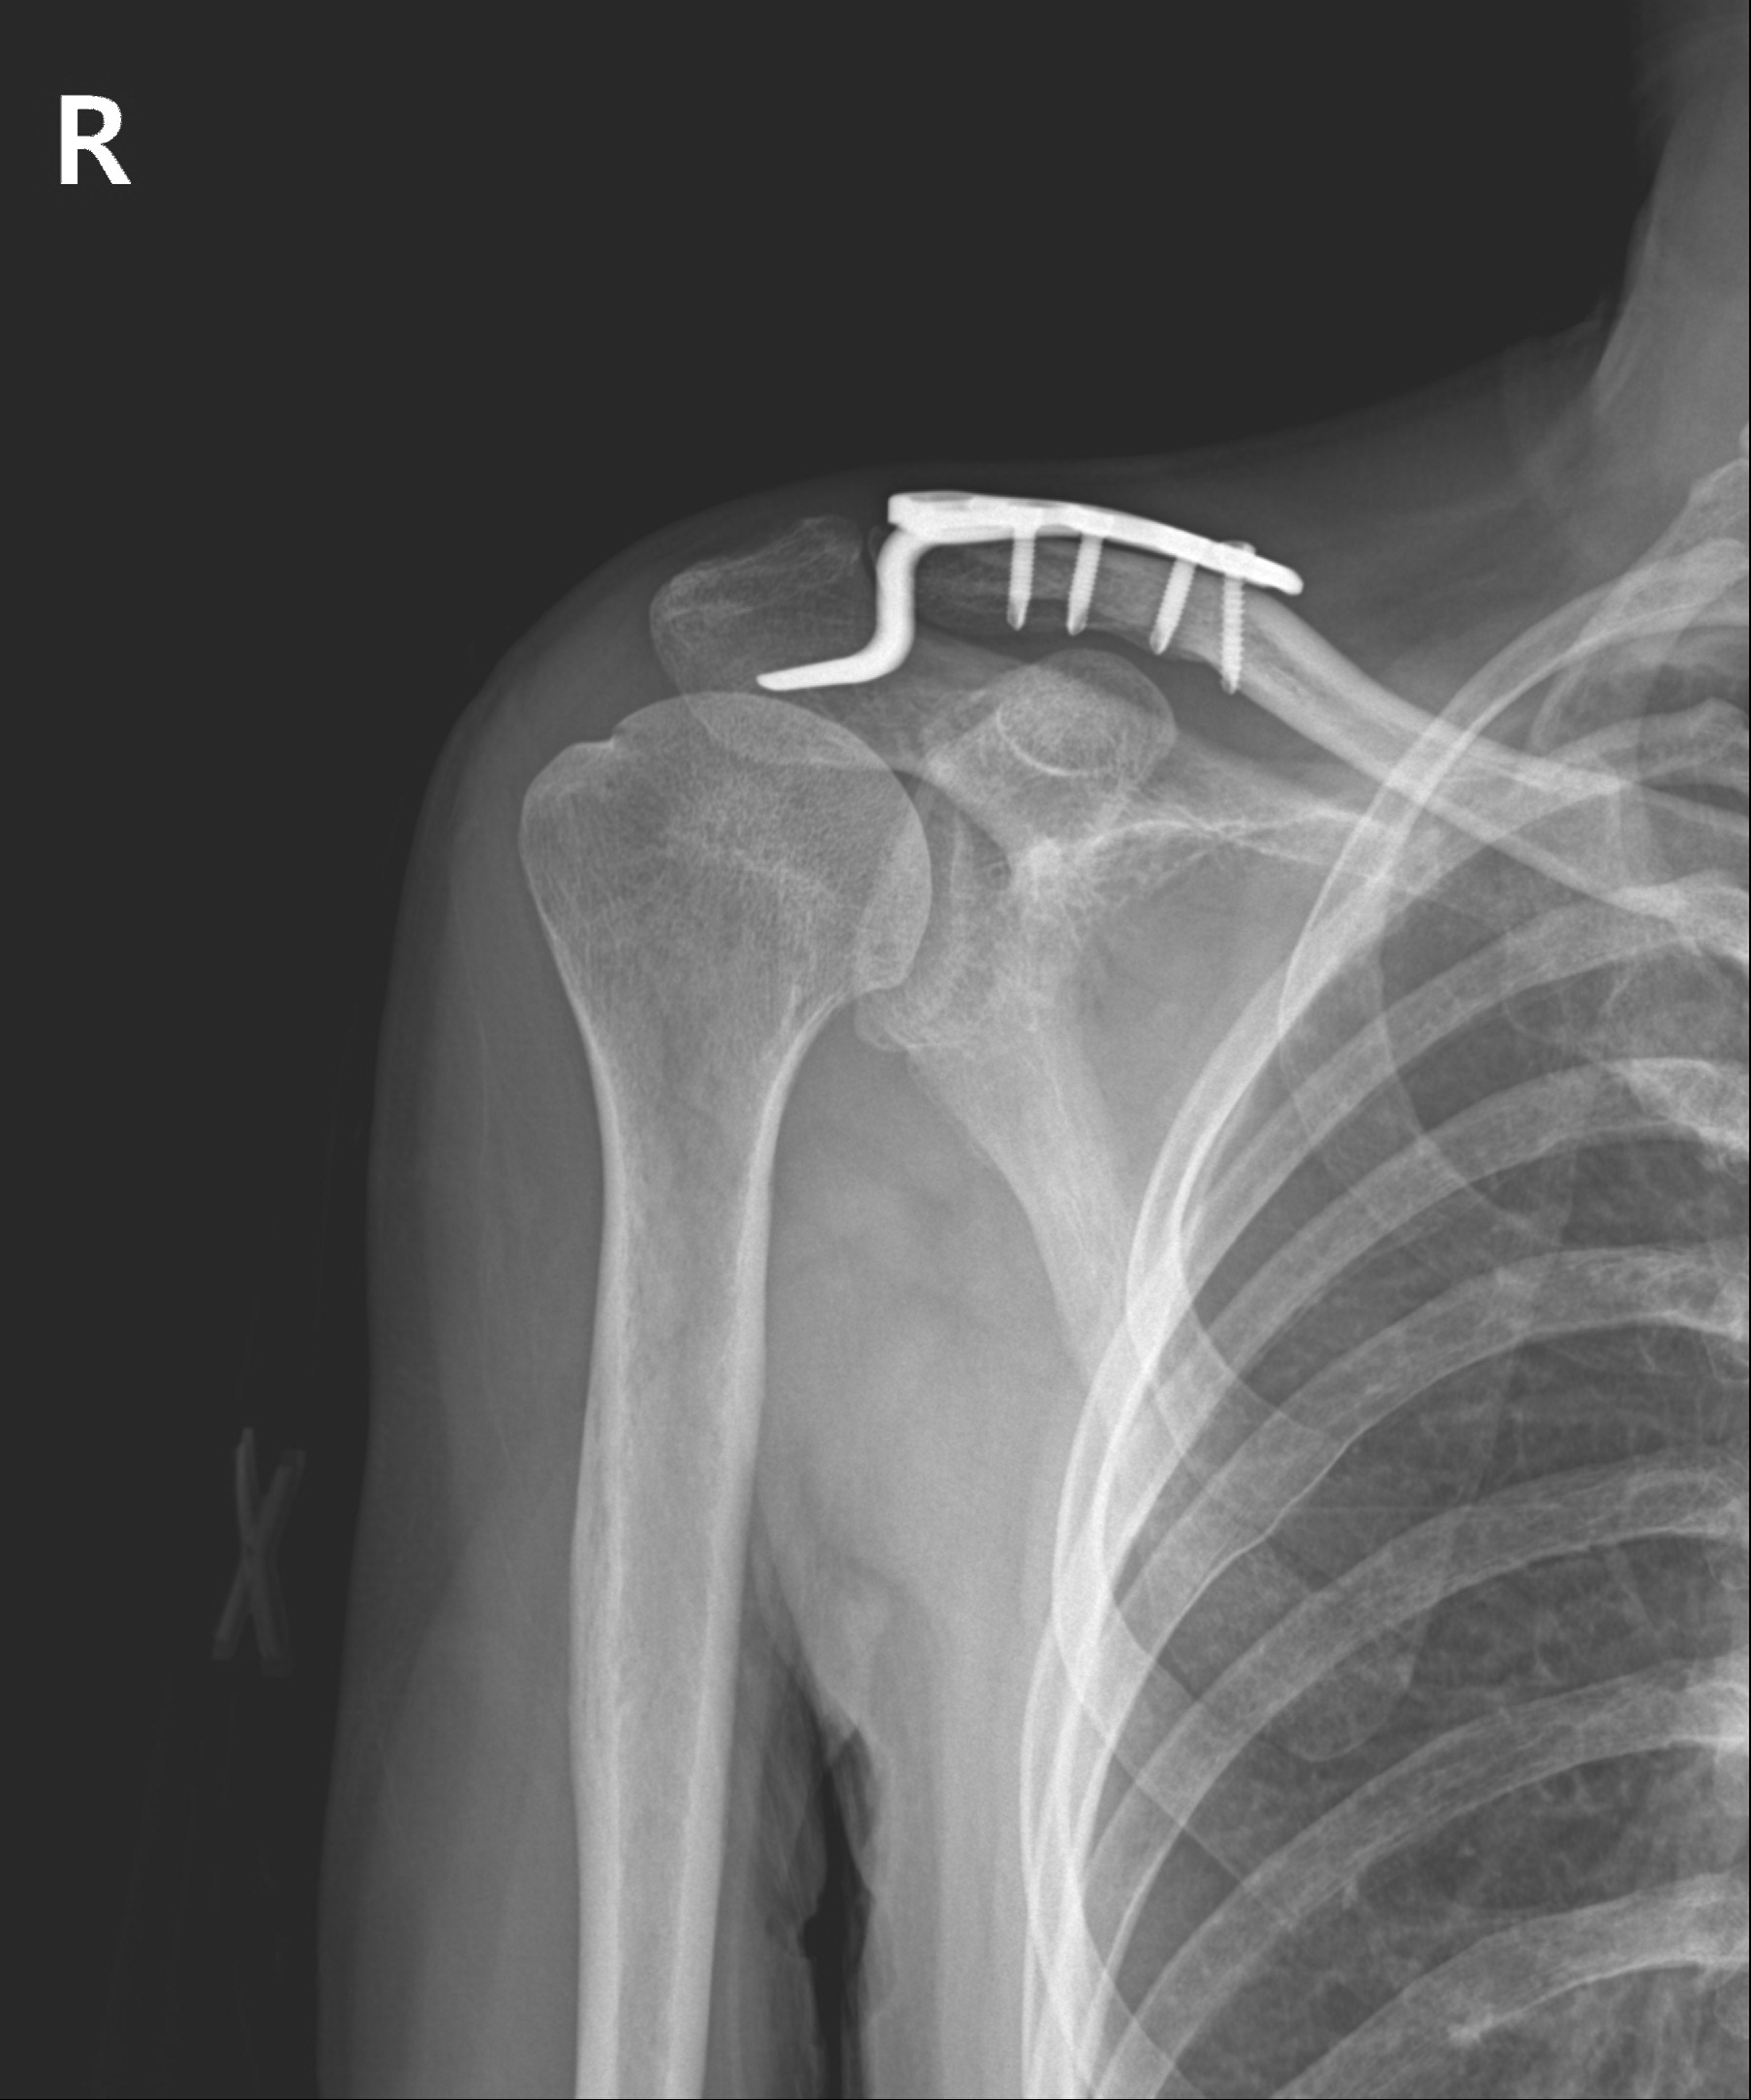

견쇄관절 탈구

2022.10.04

2022.12.27